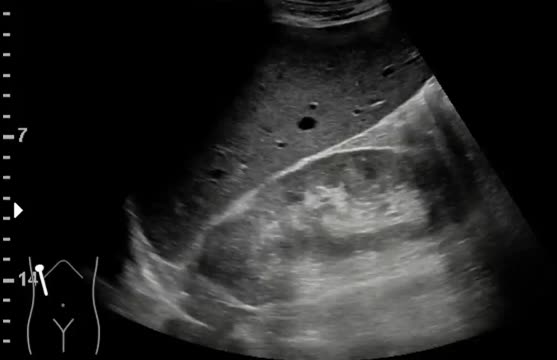

Ecográficamente es imposible distinguir entre los diferentes tipos de carcinoma renal. Normalmente se observa una masa renal sólida, generalmente heterogénea, dependiente de la corteza renal, más o menos exofítica, de predominio hipoecogénico. Las lesiones de muy pequeño tamaño suelen pasar desapercibidas con ecografía. Cuando se observa una lesión sólida hiperecogénica suele indicar presencia de grasa y por tanto podría tratarse de un angiomiolipoma, pero no siempre es así, por lo que, dependiendo del tamaño, las características y los síntomas (hematuria) y/o factores de riesgo del paciente puede estar indicado una TAC o una RMN. Durante la ecografía es importante utilizar el Doppler color para valorar la vascularización intralesional, que en caso de confirmarse es un criterio de malignidad, pero en los casos en los que el Doppler sea negativo no indica benignidad. Otro dato importante es la morfología de la lesión. Cuando una lesión es redondeada y de bordes bien definidos, se sospecha benignidad; mientras que una lesión de bordes mal definidos o lobulados es más sospechosa de malignidad15 (fig. 4 y video 5).

Los tumores vesicales se observan como lesiones sólidas, generalmente polipoideas, dependientes de pared, que no se movilizan con los cambios posturales del paciente (fig. 5).

Una vez que se detecta la lesión sólida de crecimiento intraluminal es importante utilizar el Doppler color para ver si presenta vascularización, pero en caso de tener Doppler positivo no indica más criterios de malignidad ni de agresividad del tumor16.